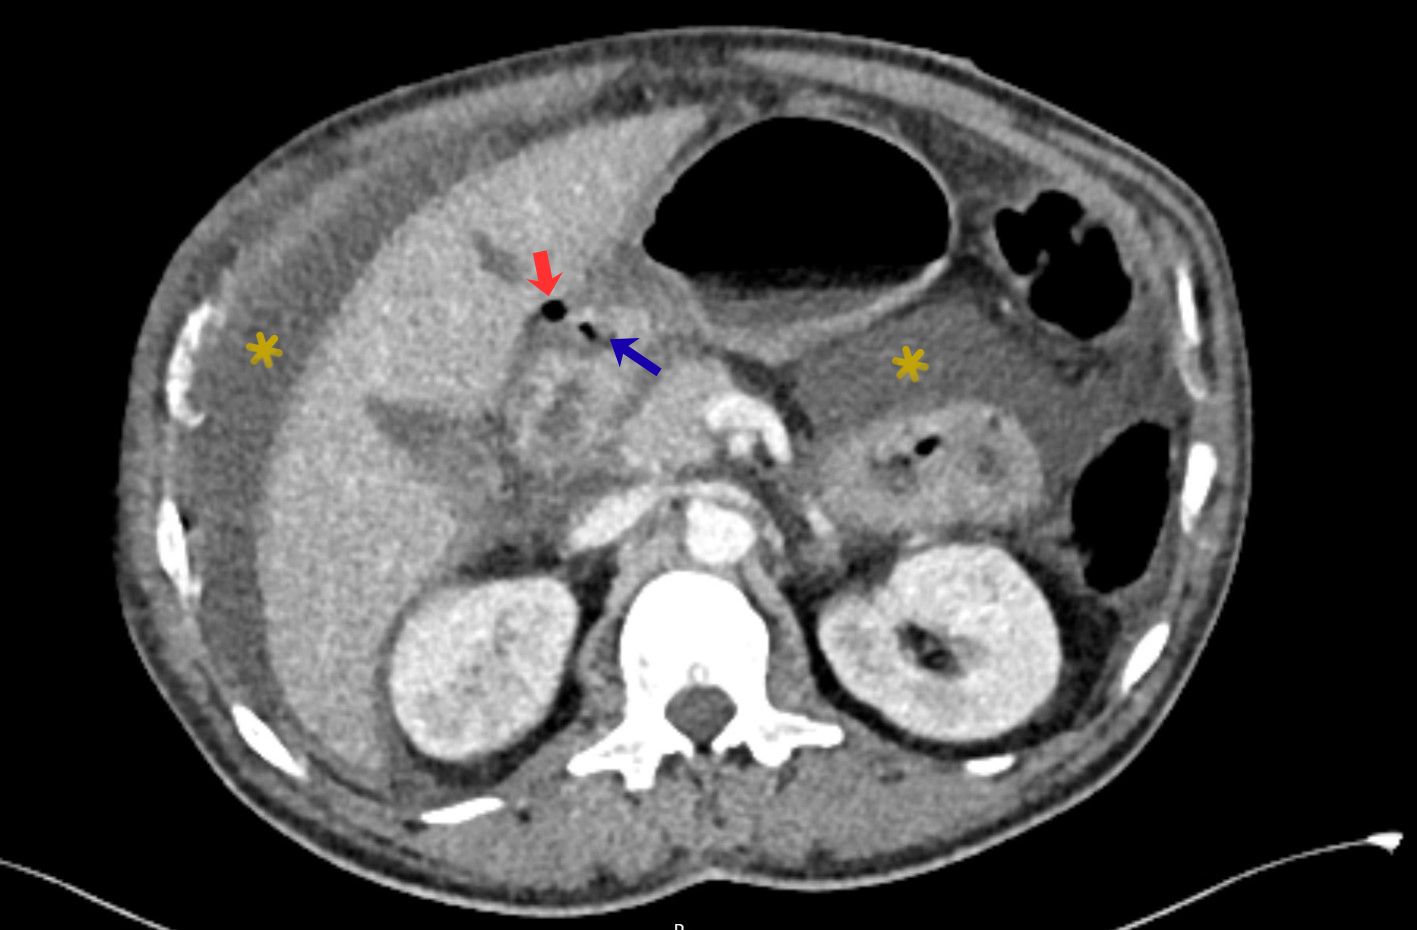

FIGURE 4: Axial contrast-enhanced CT reveals a focal defect of the anterior duodenal wall (blue arrow), with adjacent extraluminal free gas in the hepatoduodenal ligament. Associated free intraperitoneal fluid is noted within the peritoneal recesses (yellow asterisks). These findings are highly suggestive of perforated duodenal ulcer.